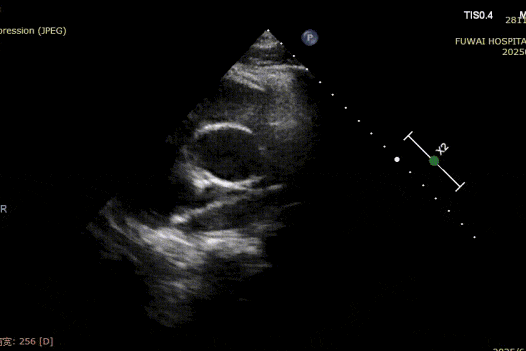

1. The ASD was central in location, with a measured diameter of approximately 8.1 mm (bicaval view) and 8.2 mm (aortic short-axis view).

4. There was no aortic rim, and the inferior and posterior rims were relatively soft.